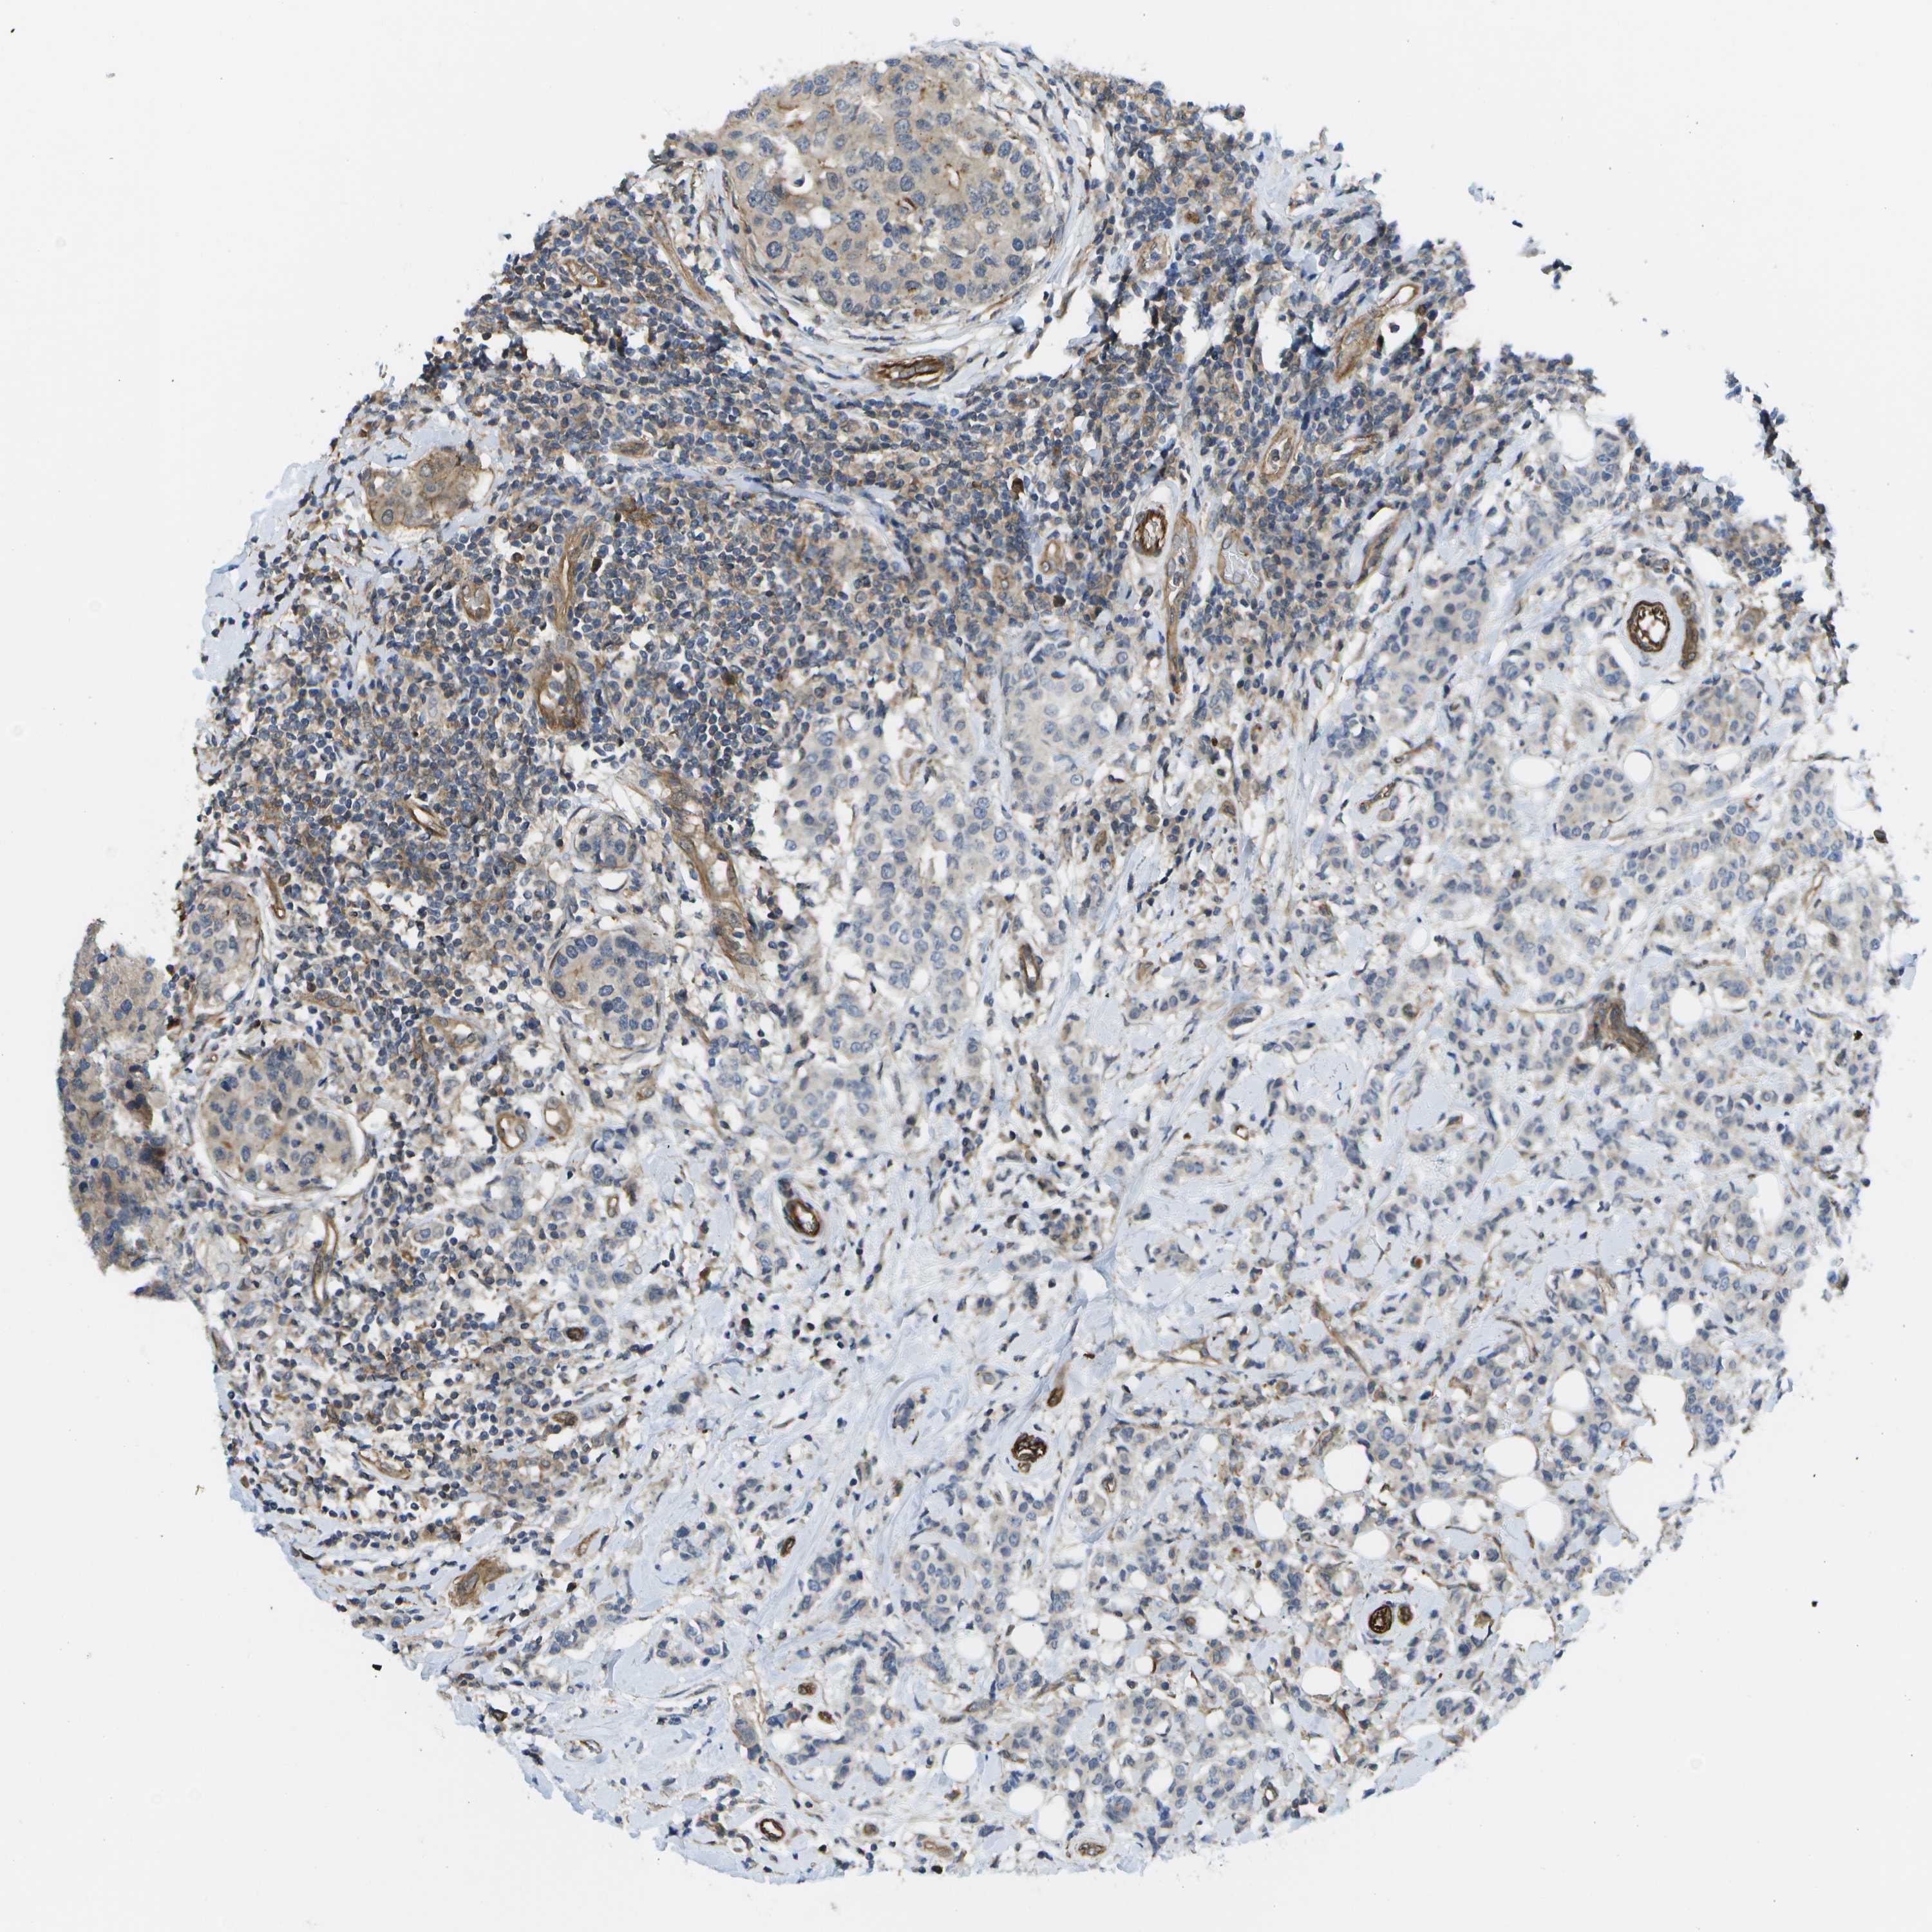

CANCER BREAST CANCER Show tissue menu

BRCA TCGA BRCA VALIDATION PROTEIN EXPRESSION

Breast cancer

Human cancer

Breast invasive carcinoma